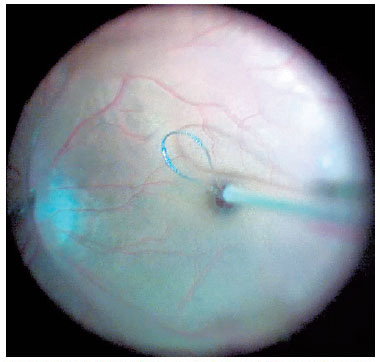

For cases in which the posterior hyaloid was attached to the posterior pole, the membrane was stained by injecting 0.1 mL of triamcinolone acetonide into the vitreous cavity and detached using a vitreous probe aspirated at a rate of 300-400 mmHg with the cutting mode turned off. The surgeon shaved the vitreous base while performing an indentation maneuver with his other hand (Figure 1). In all cases, we aimed to remove the entire vitreous base using 5,000 cuts/min with 200 mmHg aspiration power.

For macular surgery, a Machemer contact lens (Volk, Cleveland, OH, USA) was used, and the ILM was peeled using 23-gauge intraocular forceps. Peeling was initiated by grasping the ILM over the inferior macular region with the forceps or using a Finesse™ flex loop to create an ILM flap (Figure 3), and then it was extended in a circum ferential manner over the area, including the macula, without touching the retinal surface (Figure 4).